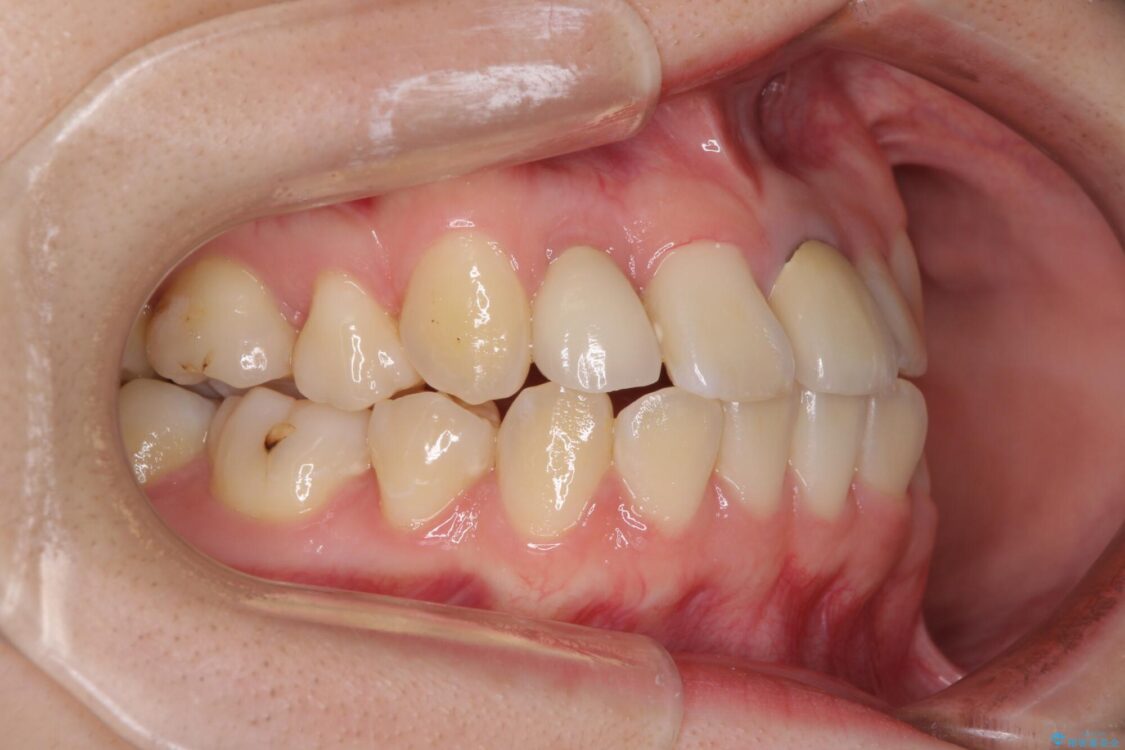

治療前

• 虫歯治療ついでに歯並びの後戻りを改善 インビザラインによる矯正治療 治療前画像

奥歯が痛いとのことで来院された患者様です。

上顎親知らず周辺の炎症と、神経組織の失活した歯の炎症による痛みが認められたため、親知らずの抜歯と根管治療を行いました。

根管治療を行った歯はクラウンによる補綴治療が必要となりますが、高校生の頃に行った矯正治療の後戻りも気になるとのことで、補綴治療を行う前に矯正治療を行うこととしました。

後戻りは軽度であり、インビザラインにて歯列を整え、その後にオールセラミッククラウンにて補綴治療を行うこととしました。